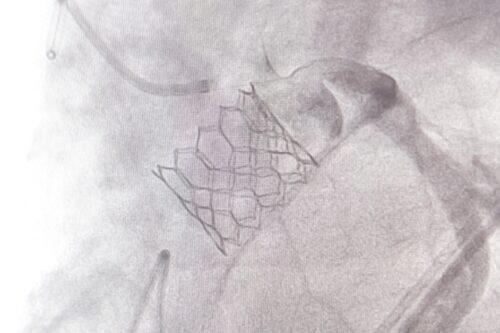

(วันที่ 2 ธค. 2568) ศูนย์หัวใจสิริกิติ์ ภาคตะวันออกเฉียงเหนือ ยกระดับการรักษาผู้ป่วยโรคลิ้นหัวใจเอออร์ติกตีบรุนแรง ด้วยหัตถการ TAVI (Transcatheter Aortic Valve Implantation) หรือการเปลี่ยนลิ้นหัวใจเอออร์ติกโดยไม่ต้องผ่าตัดเปิดหน้าอก ซึ่งเป็นเทคโนโลยีที่ช่วยลดความเสี่ยงและเพิ่มความปลอดภัย โดยเฉพาะในผู้ป่วยสูงอายุหรือผู้ที่ไม่เหมาะสมต่อการผ่าตัดใหญ่

รศ.นพ.ดนณ แก้วเกษ อายุรแพทย์หัวใจและหลอดเลือด กล่าวว่า โรคลิ้นหัวใจเอออร์ติกตีบขั้นรุนแรงเป็นภาวะที่พบได้มากในผู้สูงอายุ และอาจนำไปสู่อาการเหนื่อยง่าย เจ็บหน้าอก เวียนศีรษะ หรือภาวะหัวใจล้มเหลวได้ การรักษาแบบดั้งเดิมคือการผ่าตัดเปิดหน้าอกเพื่อเปลี่ยนลิ้นหัวใจ แต่ผู้ป่วยบางรายมีความเสี่ยงสูง ไม่เหมาะกับการผ่าตัด วิธี TAVI จึงเข้ามามีบทบาทสำคัญ ซึ่งข้อดีของ TAVI คือไม่ต้องเปิดหน้าอก ไม่ต้องหยุดหัวใจ โดยแพทย์จะผ่าตัดใส่ลิ้นหัวใจเทียมผ่านทาง หลอดเลือดแดงที่ขาหนีบ ทำให้ผู้ป่วยฟื้นตัวเร็วมาก หลายรายกลับบ้านได้ภายใน 2–3 วัน

ในส่วนของขั้นตอนการรักษา ศูนย์หัวใจสิริกิติ์ฯ ใช้เทคโนโลยีลิ้นหัวใจรุ่นใหม่ที่พัฒนาให้วางตำแหน่งได้แม่นยำ ลดความเสี่ยงของภาวะแทรกซ้อน เช่น เลือดออก หลอดเลือดบาดเจ็บ หรือการนำไปสู่ภาวะการเต้นผิดจังหวะ ทีมแพทย์ Heart Team ซึ่งประกอบด้วยแพทย์โรคหัวใจ แพทย์หัตถการ แพทย์ศัลยกรรมหัวใจ วิสัญญีแพทย์ และทีมพยาบาลเฉพาะทาง จะร่วมกันวางแผนการรักษาและประเมินอย่างละเอียดในผู้ป่วยแต่ละราย เพื่อให้ได้ผลลัพธ์ที่ปลอดภัยที่สุด